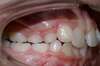

Intra Orale Gauche